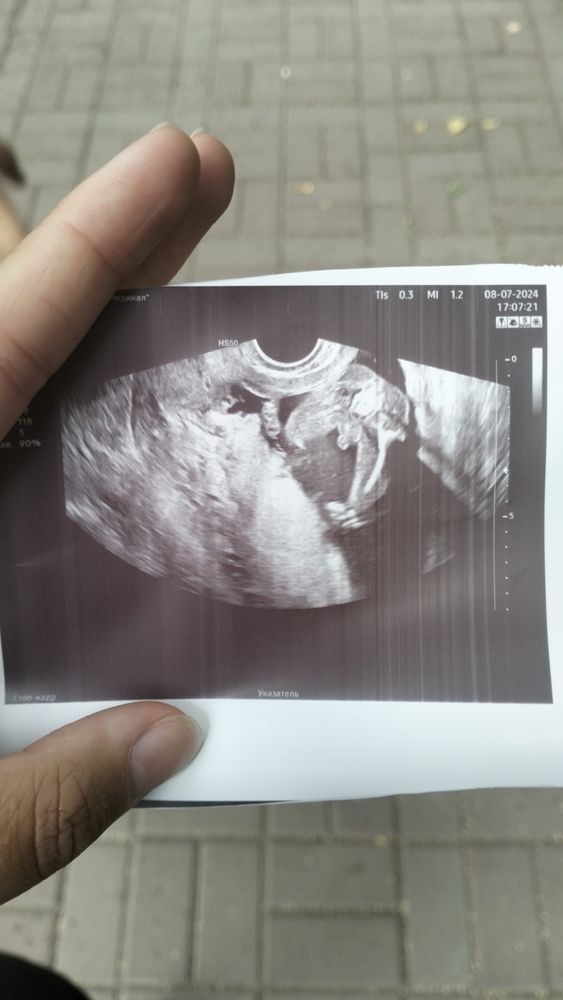

Срок 17 недель сказали что мальчик, мамочки у кого мальчики есть ,точно пацан тут ?

Да, и ещё, по-моему, не из стеснительных 🤣